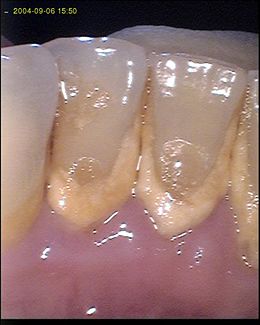

| Fig.1. Gengivite |

A alteração progressiva da massa e da composição da placa bacteriana ocorre em poucos dias, mas afecta muito significativamente os componentes do compartimento coronal. O tecido de conexão da gengiva é progressivamente destruído, e o seu lugar é ocupado por um infiltrado inflamatório. O epitélio de união sofre também alterações morfológicas importantes, mas mantém-se unido à superfície do esmalte. As fibras gengivais são parcialmente destruídas, mas o seu limite apical conserva-se ainda íntegro.Todas estas alterações caracterizam a gengivite.